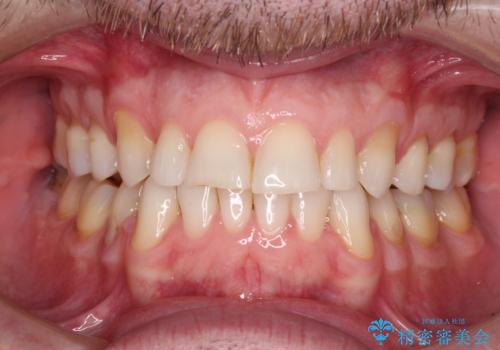

インビザラインチェンジで成功 インビザラインで八重歯の抜歯矯正

前歯が気になる 大人のマウスピース矯正 矮小歯を整える

出っ歯 下の歯のガタガタ 下の前歯のみ1本抜歯 マウスピースで1年